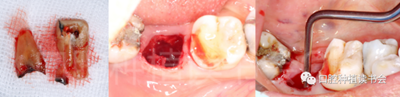

圖1 無法保留的上頜隱裂后牙,拔牙后即刻種植。

后牙區(qū)或者是非美學(xué)區(qū)即刻種植,對(duì)于患者和臨床醫(yī)生而言,存在一些明顯的優(yōu)勢(shì);比如更小的外科創(chuàng)傷、更短的愈合周期、更少的椅旁時(shí)間、更高的患者接受度以及更低的治療費(fèi)用等。除此之外,在上頜后牙區(qū)即刻種植還可以減少上頜竇的氣化現(xiàn)象【Sharan等.2008】;但并非所有的后牙位點(diǎn)都適合即刻種植,后牙區(qū)即刻種植對(duì)醫(yī)生的技術(shù)和經(jīng)驗(yàn)要求更高;由于解剖等諸多條件的差異,美學(xué)區(qū)即刻種植的臨床注意事項(xiàng)與后牙區(qū)即刻種植存在諸多不同之處;與本文旨在通過詳細(xì)的文獻(xiàn)回顧及臨床案例對(duì)后牙區(qū)即刻種植治療提供臨床參考。